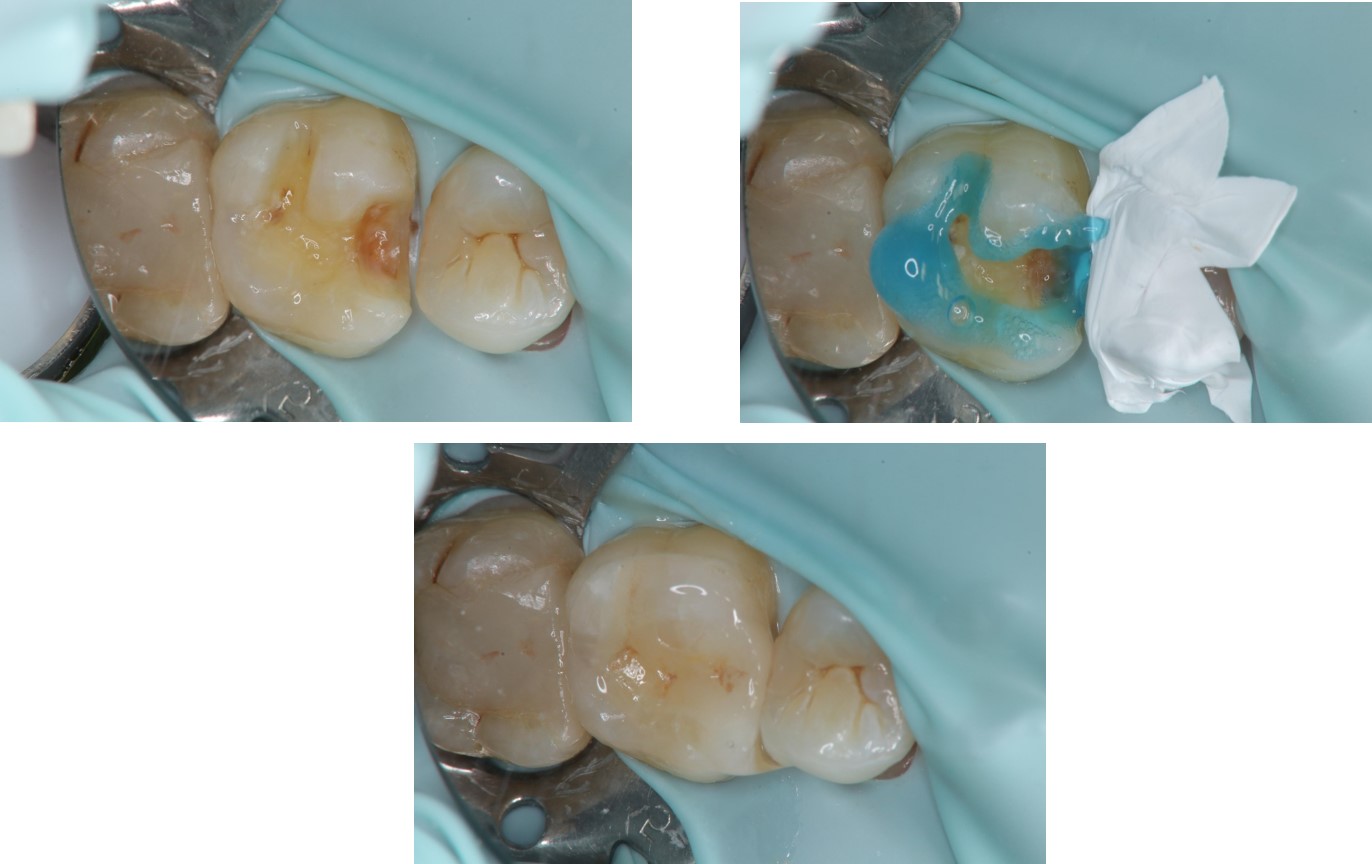

治療前,大臼齒冷熱敏感

上橡皮障,隔水,黏著瓷塊